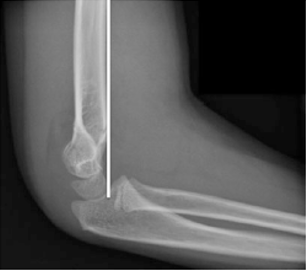

Hình 2: Gãy trên lồi cầu xương cánh tay Gartland độ IIA , đầu gãy xa duỗi so với đường trước xương cánh tay (đường trắng). Ở những trường hợp khuỷu không tổn thương ở trẻ trên 4 tuổi, đường trước xương cánh tay đi qua 1/3 giữa lồi cầu ( Courtesy of Joshua M. Abzug, MD)